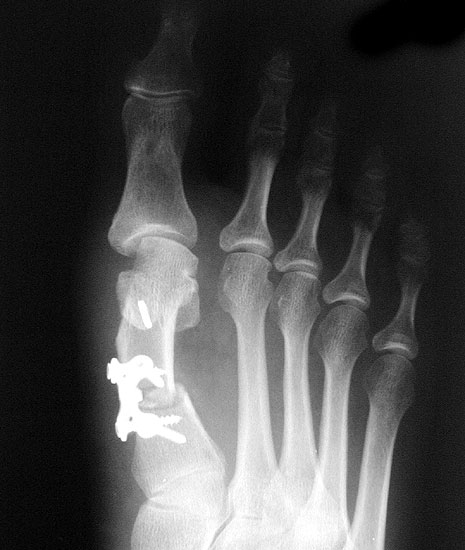

Beim Follow up nach 6 Monaten zeigte sich eine Korrektur des ersten Intermetatarsalwinkels (IMW) um durchschnittlich 9° (Range 4-15°) auf Normwerte (6,8° SD 1,3) (Abb. 21).

Gutes postoperatives Ergebnis mit physiologischem Intermetatarsale I-II Winkel nach open wedge Osteotomie.

Abbildung 21